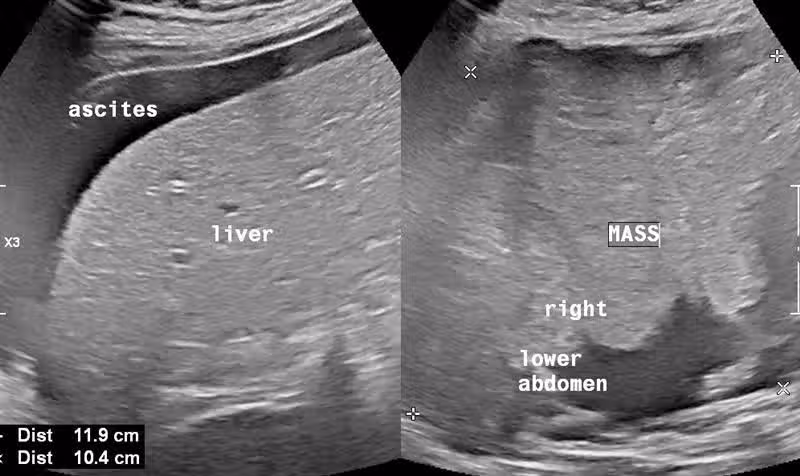

醫師謝文斌在臉書發文分享案例,一位50歲女子上周三因肚子悶痛前往社區衛生所看診,不過並非劇烈痛,是一種說不上來的不舒服。

不過乍看之下病人神色自若,不像有極度疼痛的病症。

於是再追問病史後,平常身體很好沒什麼在看病、也沒有慢性病在追蹤,也沒有做過健康檢查,儼然是一個健康寶寶。